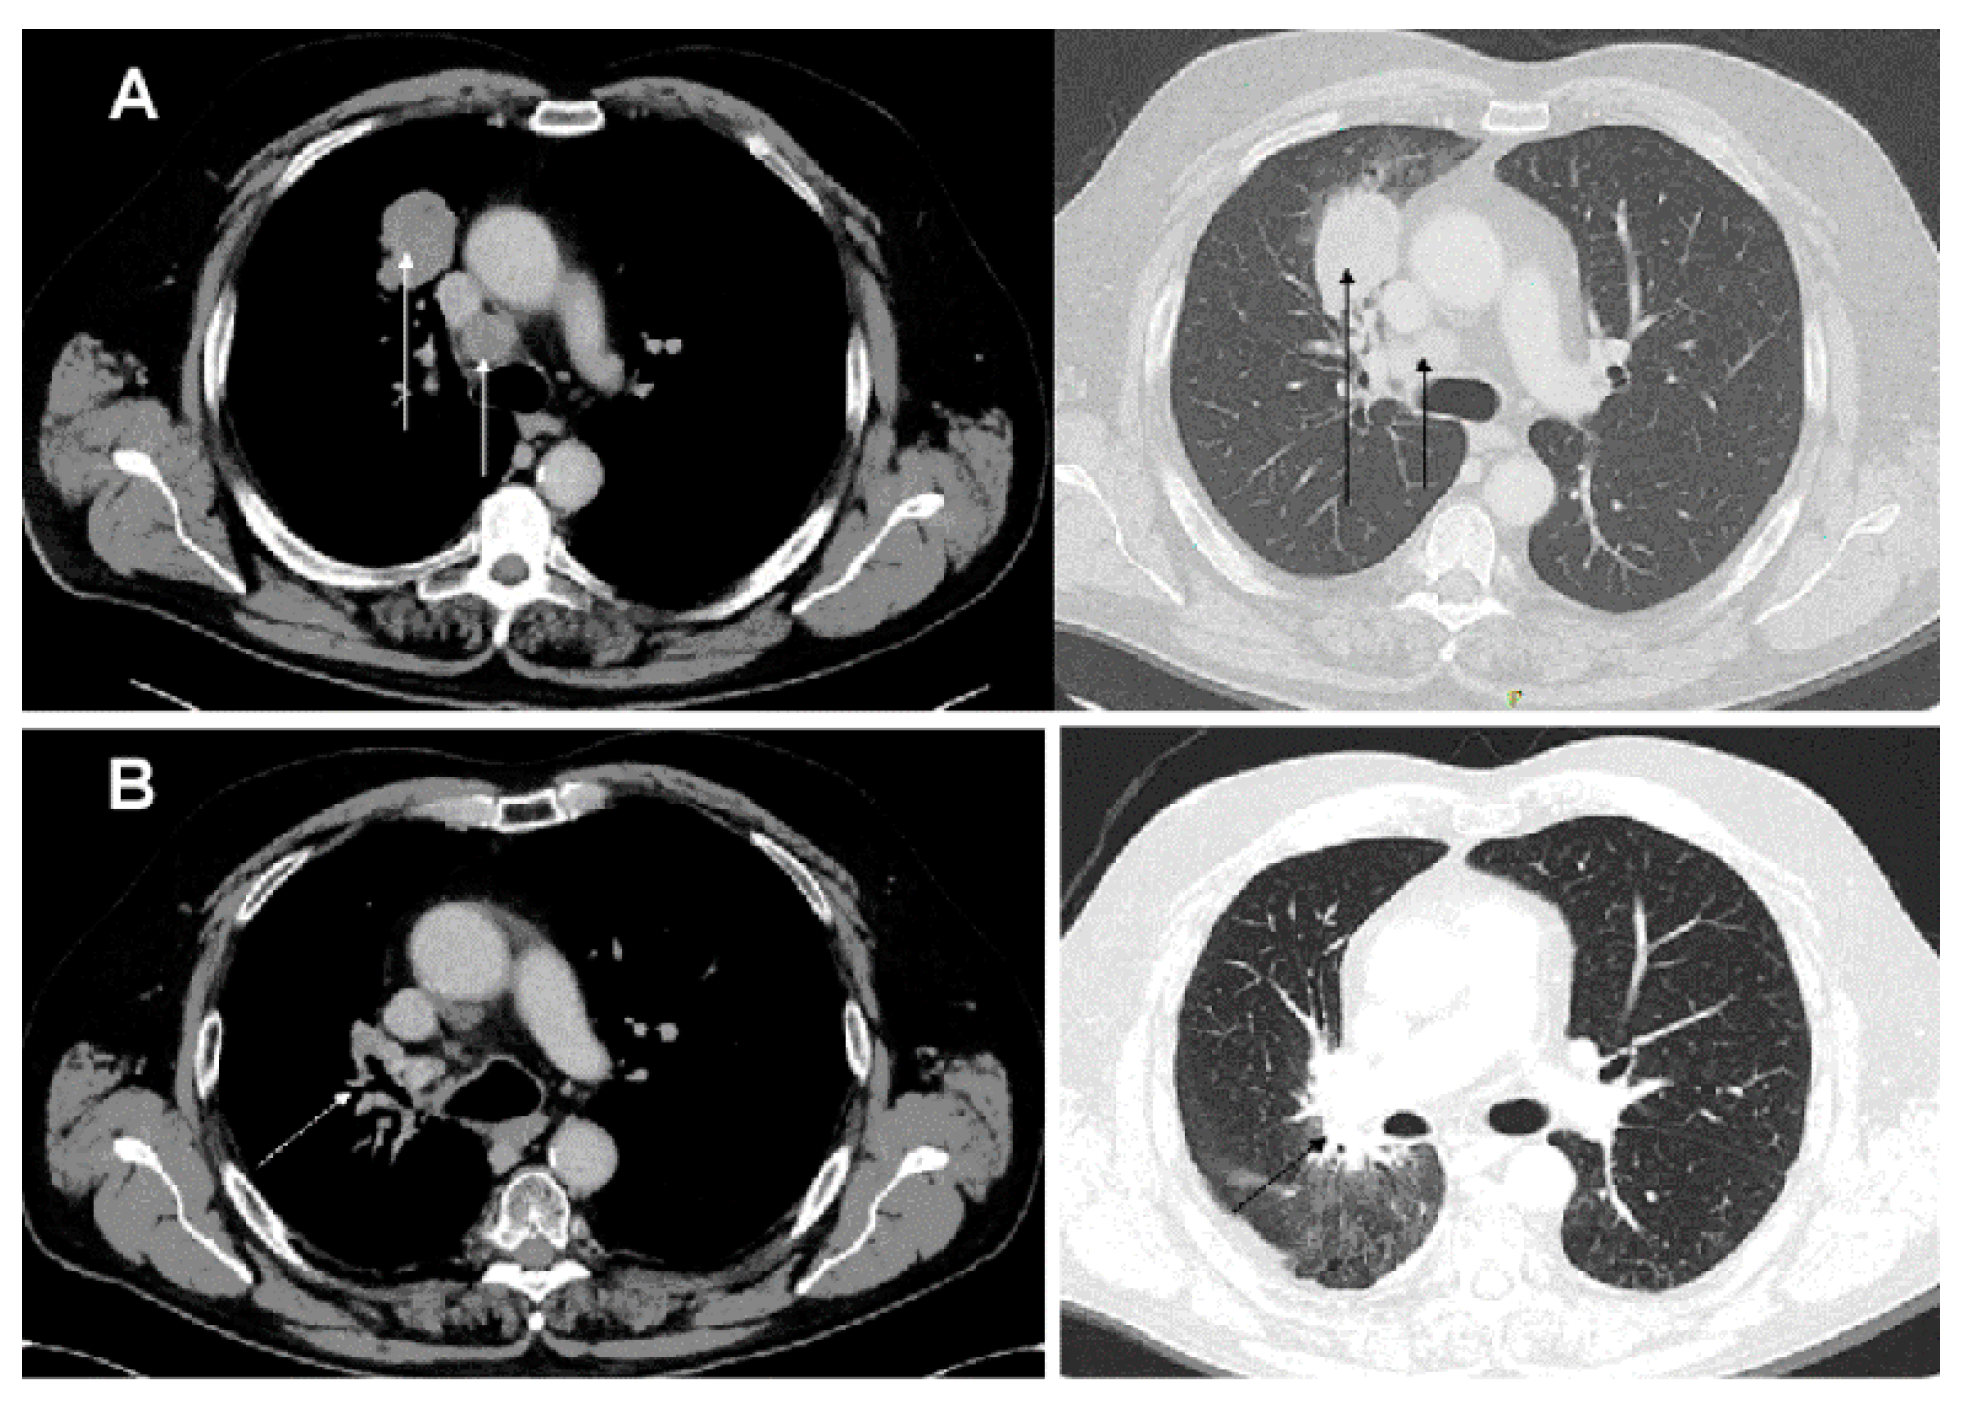

2. Case Report

4. Results